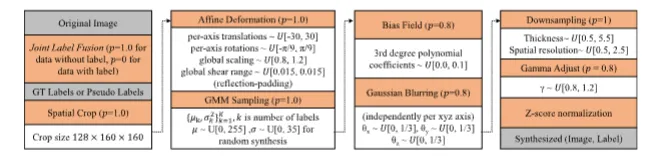

Fig. 3. Augmentation strategies (orange boxes) along with their associated probabilities (𝑝) and hyperparameters (white boxes) are presented from top to bottom,left to right. The inputs and outputs are highlighted in gray boxes. Here, μ and 𝜎 represent the mean and standard deviation, respectively. The other notationsfollow the definitions in Cardoso et al. (2022) and Avants et al. (2009)

图3 增强策略(橙色方框)及其相关概率(𝑝)和超参数(白色方框)按从上到下、从左到右的顺序呈现。输入和输出以灰色方框突出显示。其中,μ和𝜎分别表示均值和标准差,其他符号遵循Cardoso等人(2022)及Avants等人(2009)的定义。